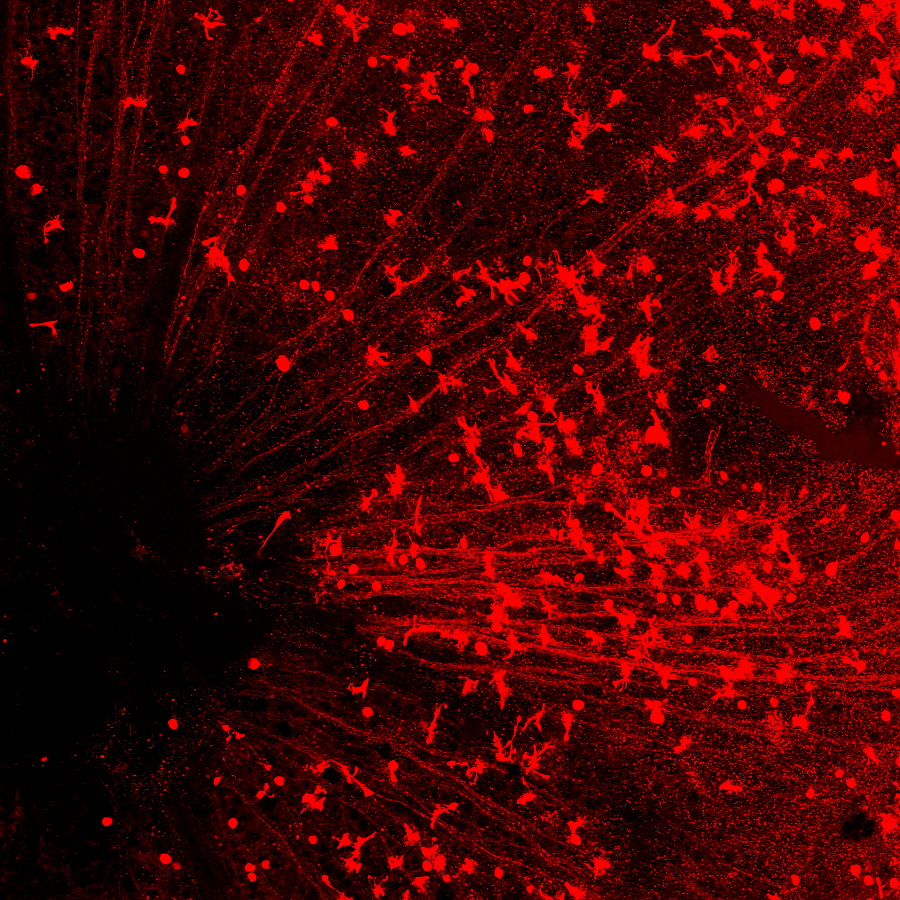

在小鼠的視網膜上,紅色圓形的細胞是再生出的視神經節細胞,可以看到一條一條的紅線匯集到眼睛中間的視盤(左下黑洞區域),這是再生出的視神經節細胞發出的軸突,它們將通過視盤傳到視神經,然后再到大腦。

視神經部位是連接眼睛和大腦的橋梁。每一條紅色的線是每一個再生出來的視神經節細胞發出的軸突,通過這里,這些新生軸突將會與大腦中處理視覺信號的區域正確相連。